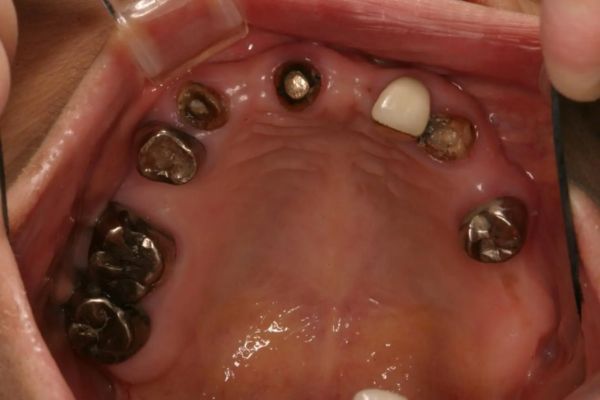

インプラント治療の症例紹介④

Before

After

主訴

義歯による疼痛

治療内容

下顎舌側に骨隆起があり義歯困難な状態。保存不可能な歯の抜歯を行い、インプラントを埋入し咬合再構成を行った。

治療費

2,851,200円(税込)

治療期間

29ヶ月

通院回数

26回

想定されたリスク

※咬合力の強い方なので、予防的にマウスピースの装着が必要。インプラント周囲炎の恐れがありました。

歯の欠損の対合歯の挺出等を修正し咬合平面を揃え咬合再構成を行った症例。